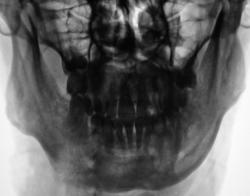

Сегодня, пациент направлен в рентгеновский кабинет для рентгенографии нижней челюсти с диагнозом "остеомиелит". Произведена рентгенография.

Ваше мнение уважаемые коллеги?

перелом нижней челюсти. Видна секвестральная полость, участки деструкции кости - остеомиелит.